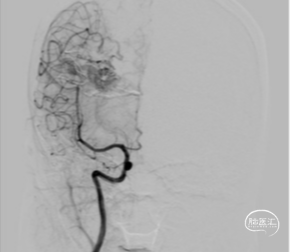

右股动脉行Seldinger穿刺,置入6F动脉鞘;益心达150cm超滑泥鳅导丝携ENVOY 6F Guiding,行右侧颈内动脉、左侧椎动脉造影。

前循环由顶叶后动脉及角回动脉吻合支供血,后循环由距状沟动脉和多支颞下动脉吻合支供血;经浅表静脉引流至上矢状窦和右侧横窦

行左椎动脉syngo Dyna3D采集,全面观察畸形团内部结构,选定工作角度,规划栓塞路径

导引导管至椎动脉V2段,工作位造影明确畸形团由距状沟动脉和颞下动脉吻合支供血

经导引导管送入微导丝+微导管,路图下超选入距状沟动脉,行微导管手推造影确认注胶位置

DMSO冲洗微导管管腔间断注入Onyx胶,期间变换角度经导引导管减影造影,确认栓塞程度

复查造影显示仍有畸形残留,使用拔打继续栓塞,直至栓塞完全